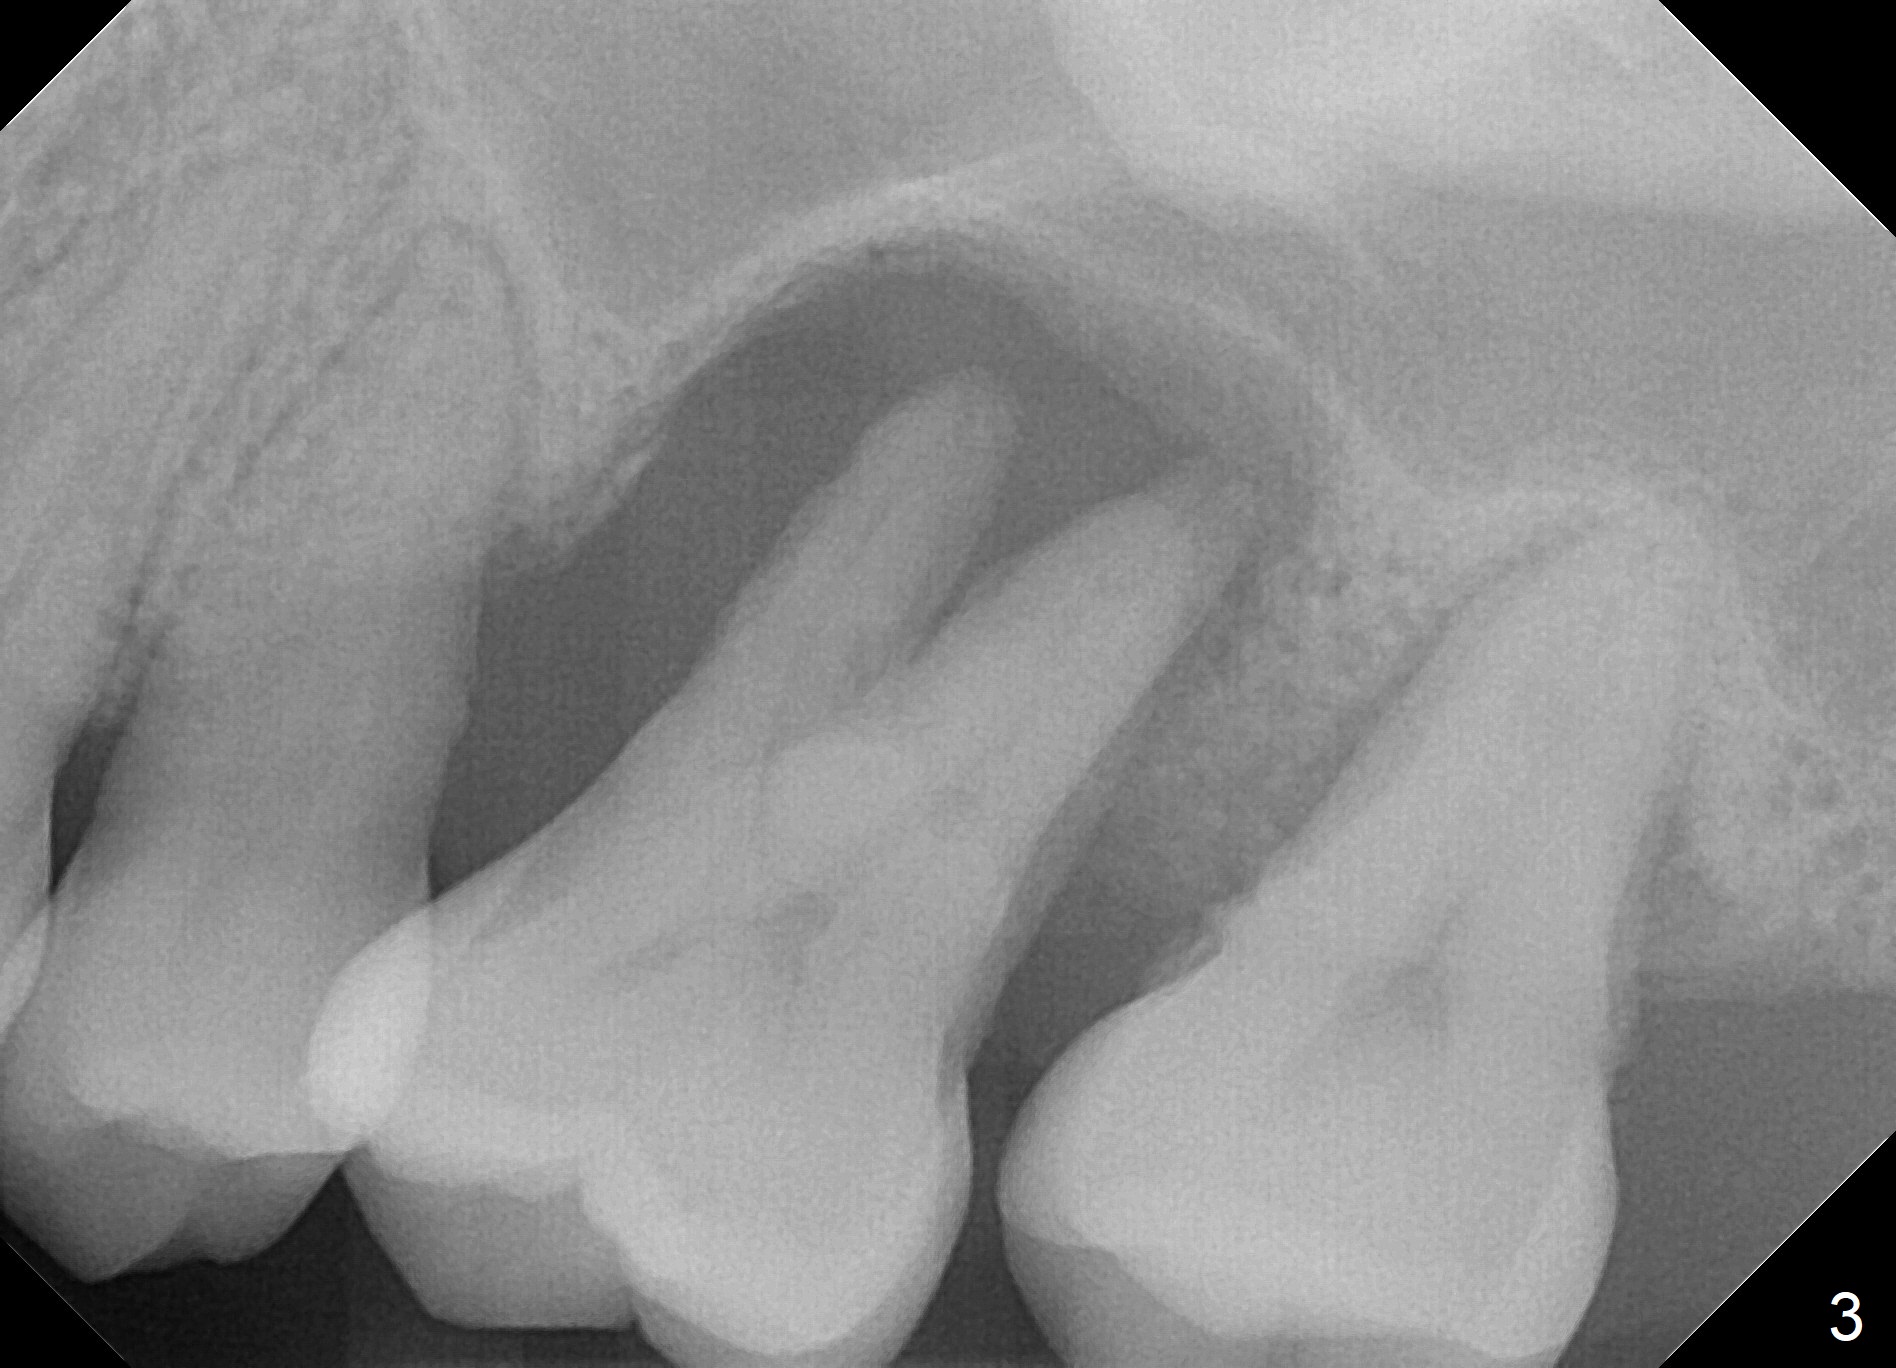

A 41-year-old man has had severe periodontitis at #14 for the last 11 years (Fig.1-3). Finally the tooth is mobile. Draw blood for PRF membrane (x4). After use of Magic Drill with 3 mm stopper, tap Magic Lifter for sinus lift. Insert 1-2 PRF membrane(s) and Vanilla graft prior to further osteotomy with UF drills until 4.5 or 5 mm. Insert tap drill for primary stability. If it fails, switch to IBS dummy implants.

3